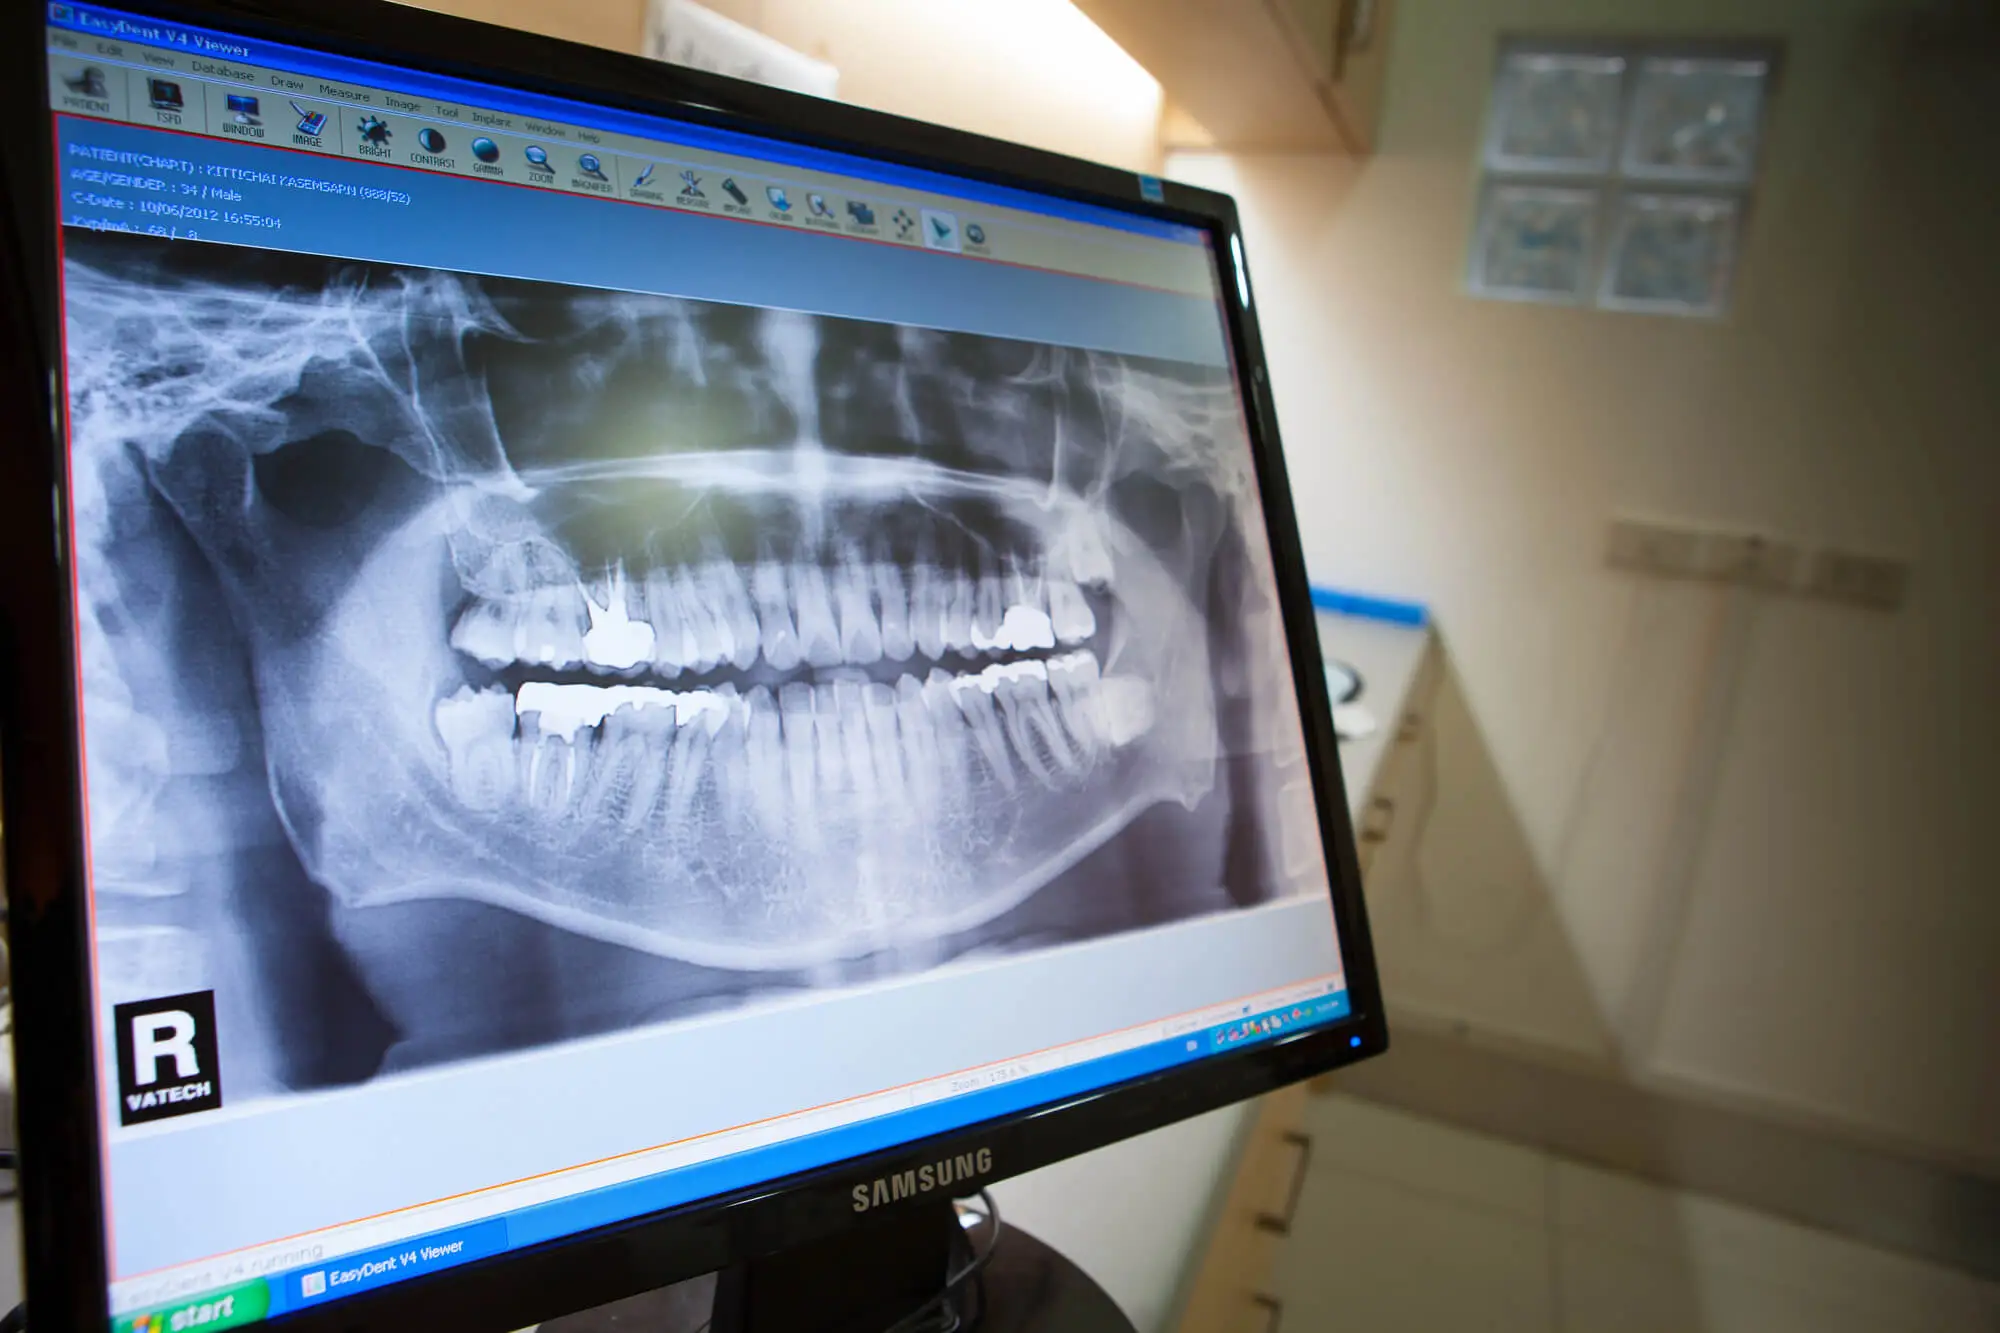

If you've recently had a dental crown placed in Queens or are considering getting one, you may be wondering how long it will last. The answer is determined by several key factors, many of which you can influence.

Dental crowns provide a long-lasting solution for restoring damaged, weakened, or missing teeth. However, like anything in your mouth, they are not indestructible. With good habits, your crown can last 10 to 15 years—but to achieve that, understanding best care practices is key.